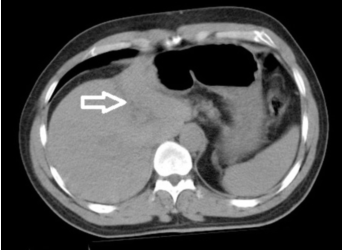

Traumatic injury, CECT

grade 2 liver injury